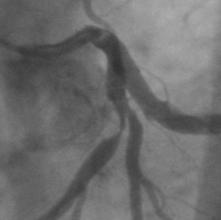

* <3 vessel reference diameters.

This case should be described as

one lesion:

- one lesion involving segments 5, 6, and 11.